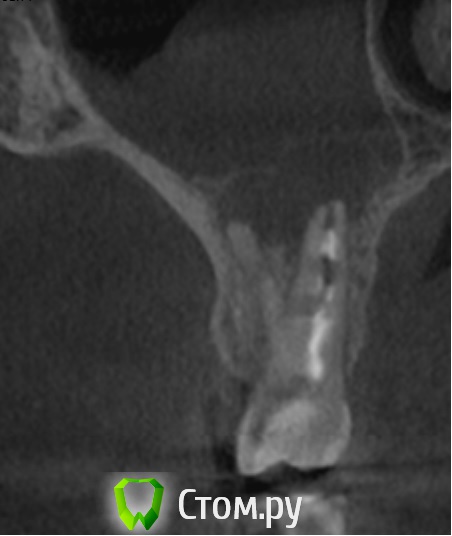

alessandor Опубликовано 8 июля, 2014 Поделиться Опубликовано 8 июля, 2014 Здравствуйте! Очень необходима Ваша консультация. Три недели назад после переутомления и переохлаждения распухла щека, никаких особых болей небыло. Сходил к стоматологу сделали снимок и компьютерное сканирование (КТ). Обнаружено обазование на корне 6 верхнего правого зуба (на снимке третий слева верхний зуб) и в гайморовой пазухе над ним. В 2009 был удален нерв и плохо запломбирован канал. Периодически последнее время при насморке была слабая ноющая боль, а незадолго до опухоли пульсация. Каких либо истечений из носа и насморка небыло, и нет сейчас. Стал принимать антибиотики - опухоль спала, через несколько дней после окончания приема щека снова распухла (может надуло в машине). Сейчас снова принимаю антибиотики (сегодня последний день) - опухоль снова спала. Все это время нос промываю долфином - что заливаю тоже и выходит (чисто). Зуб не шатается, не выпирает, при накусывании не болит (на всякий случай ем на другую сторону). Мне предлагают удаление зуба (говорят будет перфорация) со вскрытием гайморовой пазухи и удалением поврежденной слизистой оболочки. Другие предлагают попробовать полечить. При этом никто никаких гарантий не дает - как получиться. Конечно хочется сохранить зуб и не вскрывать гайморовую пазуху которая меня не беспокоит.Посоветуйте, очень на Вас надеюсь, как поступить, куда обратиться (готов приехать в другой регион), делать надо срочно, опасаюсь что снова распухнет. Могу дополнительно прислать и другие снимки из КТ. Заранее благодарю за ответ! С уважением, Александр. Ссылка на комментарий

dr-krasnov Опубликовано 8 июля, 2014 Поделиться Опубликовано 8 июля, 2014 Картина хронического правостороннего одонтогенного синусита, периапикального абсцесса в области 16 зуба. Показано хирургическое лечение и консультация ЛОР врача. 2 Ссылка на комментарий

dr-krasnov Опубликовано 11 июля, 2014 Поделиться Опубликовано 11 июля, 2014 Там нет никакого образования. Там воспаленная слизистая, а под ней больной зуб. 5 Ссылка на комментарий